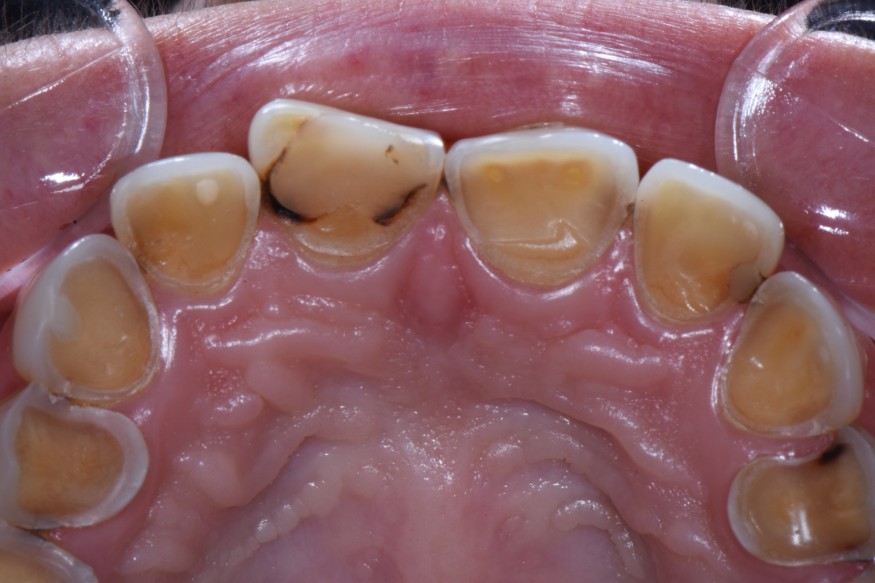

- Exposition dentinaire, due à la perte d’émail ou de cément, par abrasion (brossage traumatique), érosion (acides), attrition (bruxisme) (fig. 3-7), ou anomalies de structure (MIH**, amélogenèse imparfaite) [5].

(Source : HALEON Group) - Figure 3. Lésions érosives sévères associées à des lésions carieuses chez une patiente souffrant d’une addiction aux sodas.

(Crédit photo : Olivia Kérourédan) - Figure 4. Lésions érosives palatines au niveau du secteur incisivo-canin maxillaire, suggérant une acidité d’origine endogène.

(Crédit photo : Olivia Kérourédan) - Figure 5. Association de lésions d’usure d’origine érosive, abrasive et attritionnelle.

(Crédit photo : Olivia Kérourédan) - Figure 6. Lésions d’usure typiques provoquées par des phénomènes d’abrasion.

(Crédit photo : Olivia Kérourédan) - Figure 7. Asymétrie des lésions érosives constatée chez une patiente souffrant de reflux gastro-œsophagiens.

(Crédit photo : Olivia Kérourédan)